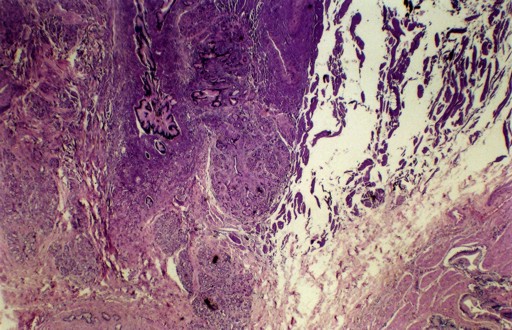

On microscopic examination of the gallbladder, a mixed chronic inflammation in the lamina propria, submucosa and muscular wall was found. The nodule showed ectopic pancreatic tissue, consisting of acini, ducts without any connection to the gallbladder lumen, and no islet cells (Figure 2).

|

Figure 2. Ectopic pancreas in the gallbladder. Pancreatic ducts, acinar component and gallbladder epithelium (H&E; original magnification x25). |